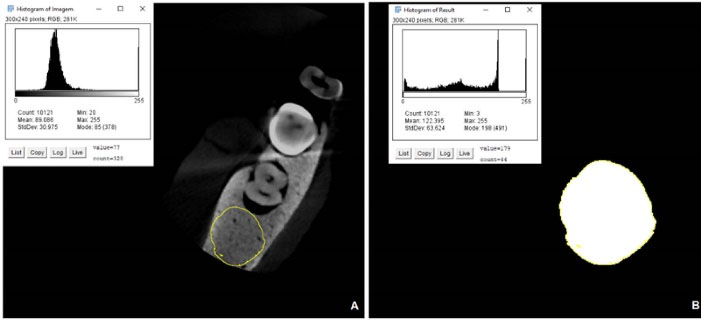

CNR measurement in CBCT images

The volumes of each sample were individually loaded into the OnDemand3D Dental software (version 2016.1). In the sagittal and coronal sections, the vertical guideline was positioned longitudinally along the long axis of the restored teeth, and the horizontal guideline was positioned on the tooth‒restoration interface, resulting in the axial reference section, which was captured and exported in BMP format, to be dealt with in the following steps, using the methodology adapted from the study by Rabelo et al.

28

In the axial image obtained, the region of the tooth was manually delimited using the free selection tool of the GIMP program. The selected structure was cut, transferred to a black background with grayscale (8-bit) in a square format measuring 10 × 10 cm, and exported in JPEG format to proceed with the precise selection of the regions of interest. This cut was necessary, as the pixels of adjacent materials had to be disregarded in the CNR calculation, and it would not have been possible to remove them in the following steps ().

Figure 2.

Manipulation of images in the GIMP program. A. Freehand selection of the restored tooth. B. Exclusion of the adjacent images

Subsequently, the images were duplicated and binarized in the Image J software. An ROI with the same size as the region of interest of the restored tooth (ROIR) was selected on the outer side of the original acquisition to be used as a control area (ROIC). For each ROI, a histogram with the standard deviation (SD) and mean grayscale values was generated ().

Figure 3.

Histogram with data for calculating the CNR. A. Histogram of ROIc. B. Histogram of the restored tooth (ROIR)

Using the values acquired, the CNR of each image could be measured according to the following equation:

where MeanR corresponded to the average gray values of the ROI of the restored tooth and MeanC to the mean of gray values of the ROI of the control area. SDR and SDC corresponded to the standard deviation of the restored tooth and the control area, respectively.